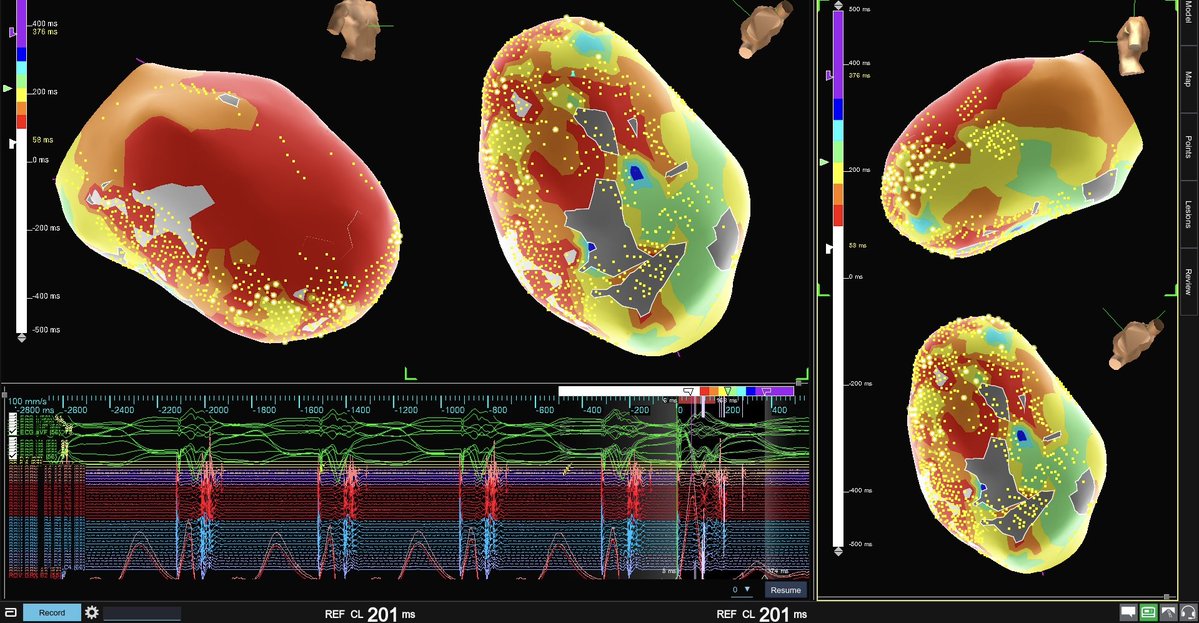

Looking back over this case and had to share these signals. #ILAM #decelzone @JRWinterfield @DrRoderickTung

Patient presented with easily inducible tachycardia (CL ~510 ms). No discernible jump, but a long PPI suggested AVNRT. Made this beautiful map utilizing #HDGrid and #VoXel mode showing colliding wavefronts at the blue lesion. Several burns here = no more tachycardia #EnsiteX